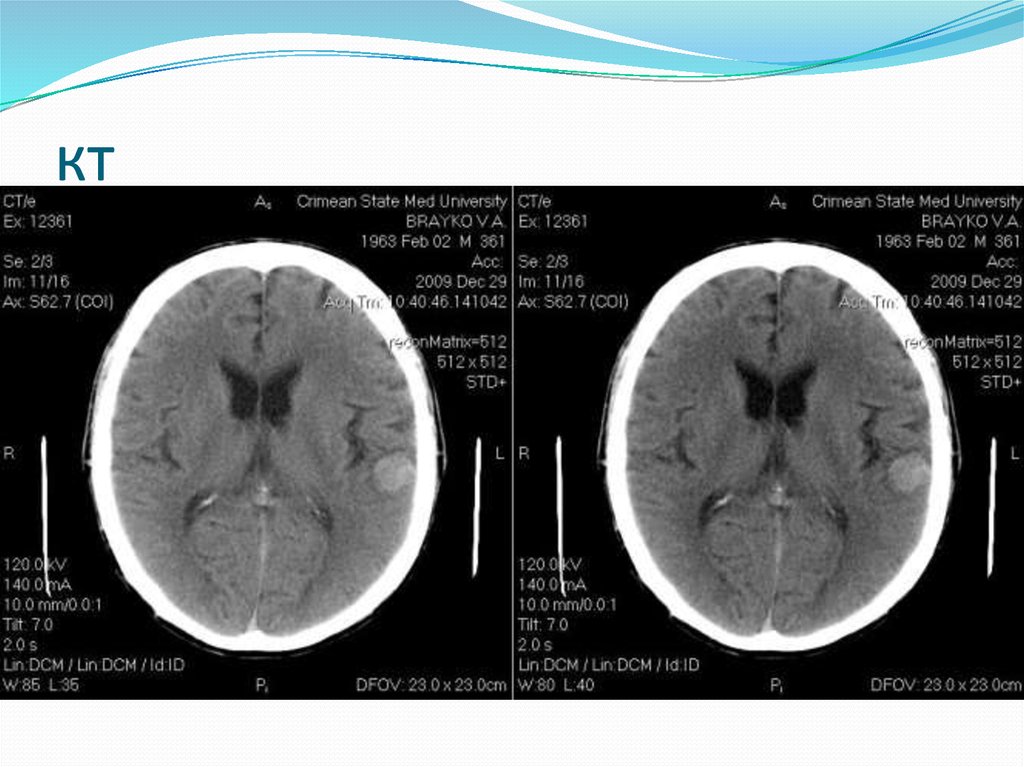

2. Олигодендроглиома

Отличительный

признак ОДГ от

других глиом —

наличие

петрификатов в

опухоли. Нередко

выявляют очаги

гетерогенного

сигнала (микрокисты

и кровоизлияния).

3. КТ